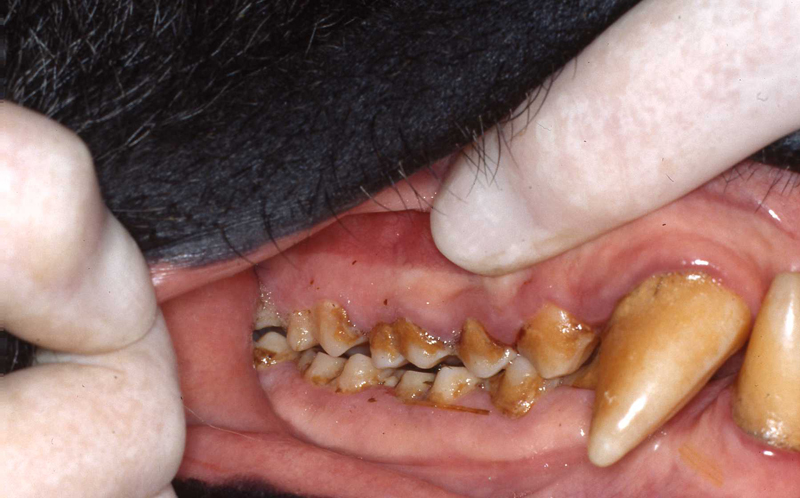

The next most common pathosis encountered is periodontal disease. Again, improvement in diets has reduced this disease. I strongly believe that besides nutrients, diet texture is very important in optimizing oral health, minimizing periodontal disease. I believe that soft or pelleted foods that do not stimulate and challenge the dentition and periodontium may contribute to periodontal disease. Duplicating natural diets in this manner for diverse species is of course, not always possible, but zoos do make efforts to do so when they can.

In the gorillas and bonobos that were born and raised here at Milwaukee County Zoo, we have not had many periodontal problems. We have had adult gorillas come to us from other zoos with significant periodontal disease.

Most or our orangutans however, have had chronic, serious periodontal disease. All of our males have eventually lost all their teeth due to periodontal disease. That has not been the case with the females. We are not the only zoo that has had the chronic periodontal problems with orangutans. See Dr. Norm Stollers' paper: In the typical orangutan case that I have dealt with, there is not much accumulation of plaque or calculus. However, deep periodontal pocketing and bone loss progresses until the teeth become very mobile. I have not observed much bleeding in the most severe of these cases. We discussed preventive strategies and even tried chlorhexidine gluconate rinses to subdue the disease process. However, the orangs did not accept the products, probably due to the taste.